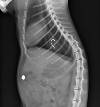

Już dawno przestało nas to szokować, stało się raczej przykrą normą. W czwartek trafił do nas kot z Pagorzyny. W USG liniowe ciało obce, w RTG haczyk wbity w przełyk w niewielkiej odległości od serca, w jelitach ołowiany ciężarek, całość połączona dratwą. Zabieg na otwartej klatce piersiowej trwał 4 godziny, haczyk utknął uszkadzając częściowo ścianę żyły głównej doogonowej. Robota sapera, ułamki milimetra dzieliły kotkę od śmierci. Później jeszcze dwa cięcia, jedno na żołądku drugie na jelicie. Tym razem się udało. Stwierdziliśmy, że to pewnie przypadek. Niestety, nie mieliśmy racji. Piątek przyniósł drugiego kota z Pagorzyny. Ten miał więcej szczęścia haczyk wbił się w żołądek, zabieg był dużo prostszy. Trudno nie podejrzewać działania celowego. Co by się stało gdybyśmy nie zdążyli na czas? Obydwa koty umierały by bardzo powoli. Haczyk zakotwiczył dratwę, ruchy jelit ciągnęły ciężarek w przeciwnym kierunku. W takiej sytuacji całe jelito nawija się na linkę, fastryguje, aż w końcu powoli coraz bardziej przecina. Niestety to bardzo przemyślane działanie. Po co Wam to piszemy? Najczęściej jest tak, że mniej lub bardziej przypadkowy świadek wie o tym, kto jest sprawcą postrzału, zatrucia, założenia wnyk czy w końcu przynęty z haczykiem. Wyrzucenia kociąt do śmietnika, utopienia szczeniąt, przywiązania psa do drzewa w lesie, znęcania się nad zwierzęciem, kłusownictwa. Jeśli o czymś takim wiecie, zgłaszajcie to policji. W przeciwnym wypadku stajecie się współwinni podobnych sytuacji. Jeśli w XXI wieki nadal otaczają nas ludzie, którzy nie potrafią się kontrolować lub swoje problemy i związane z nimi napięcia przerzucają na innych, w tym zwierzęta, to czas w taki czy inny sposób pomóc im zrozumieć co robią. Widzisz - reaguj. weterynarzgorlice.pl